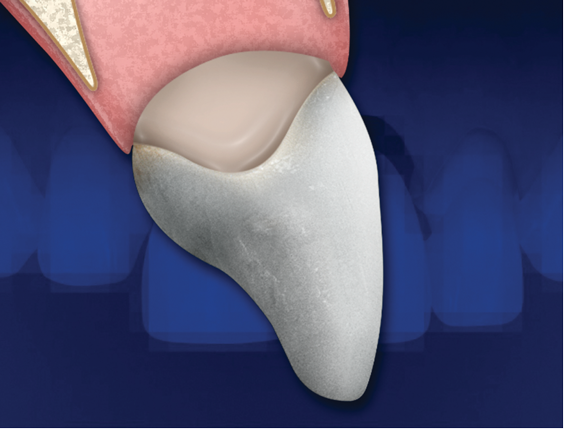

It is essential that an ovate pontic be convex in all dimensions. However, with the traditional "egg in the nest" shape, the gingival marginal tissue over the facial aspect of the pontic is commonly rolled rather than knife edged, which can result in a shadow (Figure 1) and give away that it is a pontic rather than a natural tooth. Therefore, the critical issue isn't the shape of the intaglio surface of the pontic but rather the emergence profile of the pontic on its facial surface. Where the facial aspect of an ovate pontic emerges from the soft tissue, it should have the same contour as a natural tooth. Therefore, it should not be rounded. The facial aspect of an ovate pontic should have a flat surface that goes approximately 1.0 mm under the gingival crest before it starts to become rounded (Figure 2). The shape of the rounded surface of the pontic is determined by the thickness of the ridge in the created site. It will be more round for a thick ridge and more pointed for a thin ridge.

(2.) Ovate pontics should have a flat facial surface that goes approximately 1 mm under the gingival crest before it starts to become rounded. Wider ridges will accommodate more rounded ovate pontics.

Figure 2